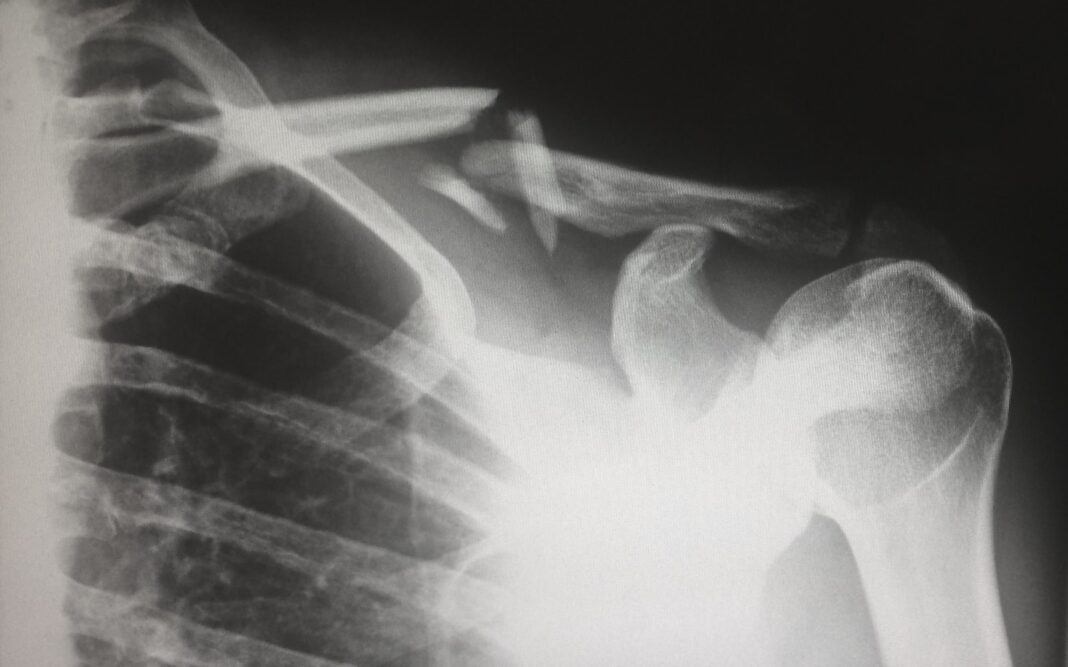

Rola RTG, USG i rezonansu magnetycznego

W celu dokładnej oceny strukturalnych uszkodzeń wykonuje się:

• RTG (zdjęcie rentgenowskie) – wykazuje przemieszczenie obojczyka; używane szczególnie w pozycjach stresowych,

• USG (ultrasonografia) – pozwala ocenić więzadła i torebkę stawową w czasie rzeczywistym,

• MRI (rezonans magnetyczny) – najbardziej dokładna metoda do wizualizacji tkanek miękkich i zakresu uszkodzenia więzadeł.

Połączenie tych metod daje precyzyjny obraz i umożliwia klasyfikację uszkodzenia według skali Rockwooda, co pomaga w dobraniu skutecznej terapii.